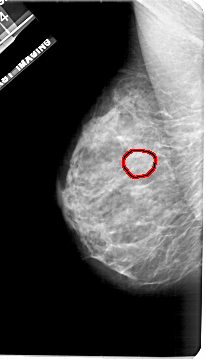

FILE: A_1921_1.LEFT_MLO.OVERLAY TOTAL_ABNORMALITIES 1 ABNORMALITY 1 LESION_TYPE MASS SHAPE OVAL MARGINS OBSCURED ASSESSMENT 3 SUBTLETY 2 PATHOLOGY BENIGN TOTAL_OUTLINES 1 BOUNDARY |